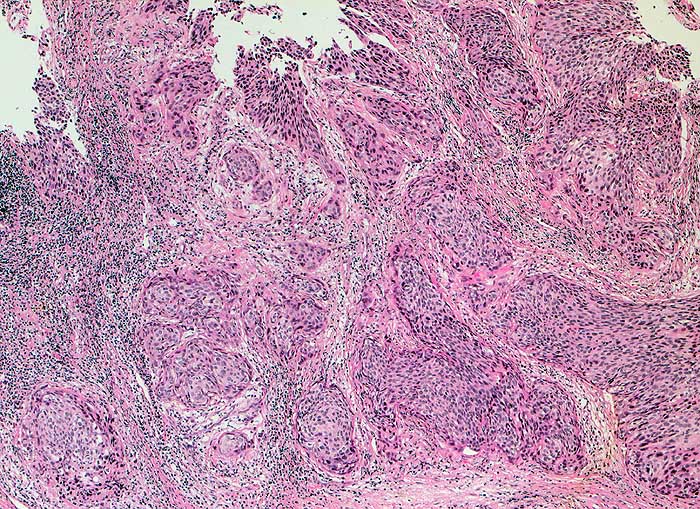

Die Tumorzellen liegen einzeln oder in kleinen Verbänden und ganzen Gewebsfragmenten. Die polymorphen Kerne sind vergrössert und enthalten verklumptes unregelmässig verteiltes Chromatin und grosse Nukleolen. Gut differenzierte Karzinome erkennt man am breiten und oft verhornten Zytoplasma. Längliche bis fadenförmige Tumorzellen mit pyknotischen Kernen können als einziger Hinweis auf das Vorliegen eines Karzinoms vorhanden sein. Wenig differenzierte Karzinome haben polymorphe und schlechter erhaltene Kerne. Der Hintergrund ist meist detritisch und oft hämorrhagisch. Ulzeration, Einblutungen und bakterielle Infektionen beeinflussen den Erhaltungszustand und die Art der abgestrichenen Zellen. Ist die Oberfläche eines ulzerierten Karzinoms von einem Fibrinschorf bedeckt, enthalten die Ausstriche lediglich Detritus, Granulozyten und Erythrozyten, aber keine Tumorzellen. Die Sensitivität für die Karzinomdiagnose ist aus diesem Grund geringer als für die Diagnose eines Carcinoma in situ.

Unten werden drei Fallbeispiele mit histologischer Korrelation gezeigt.